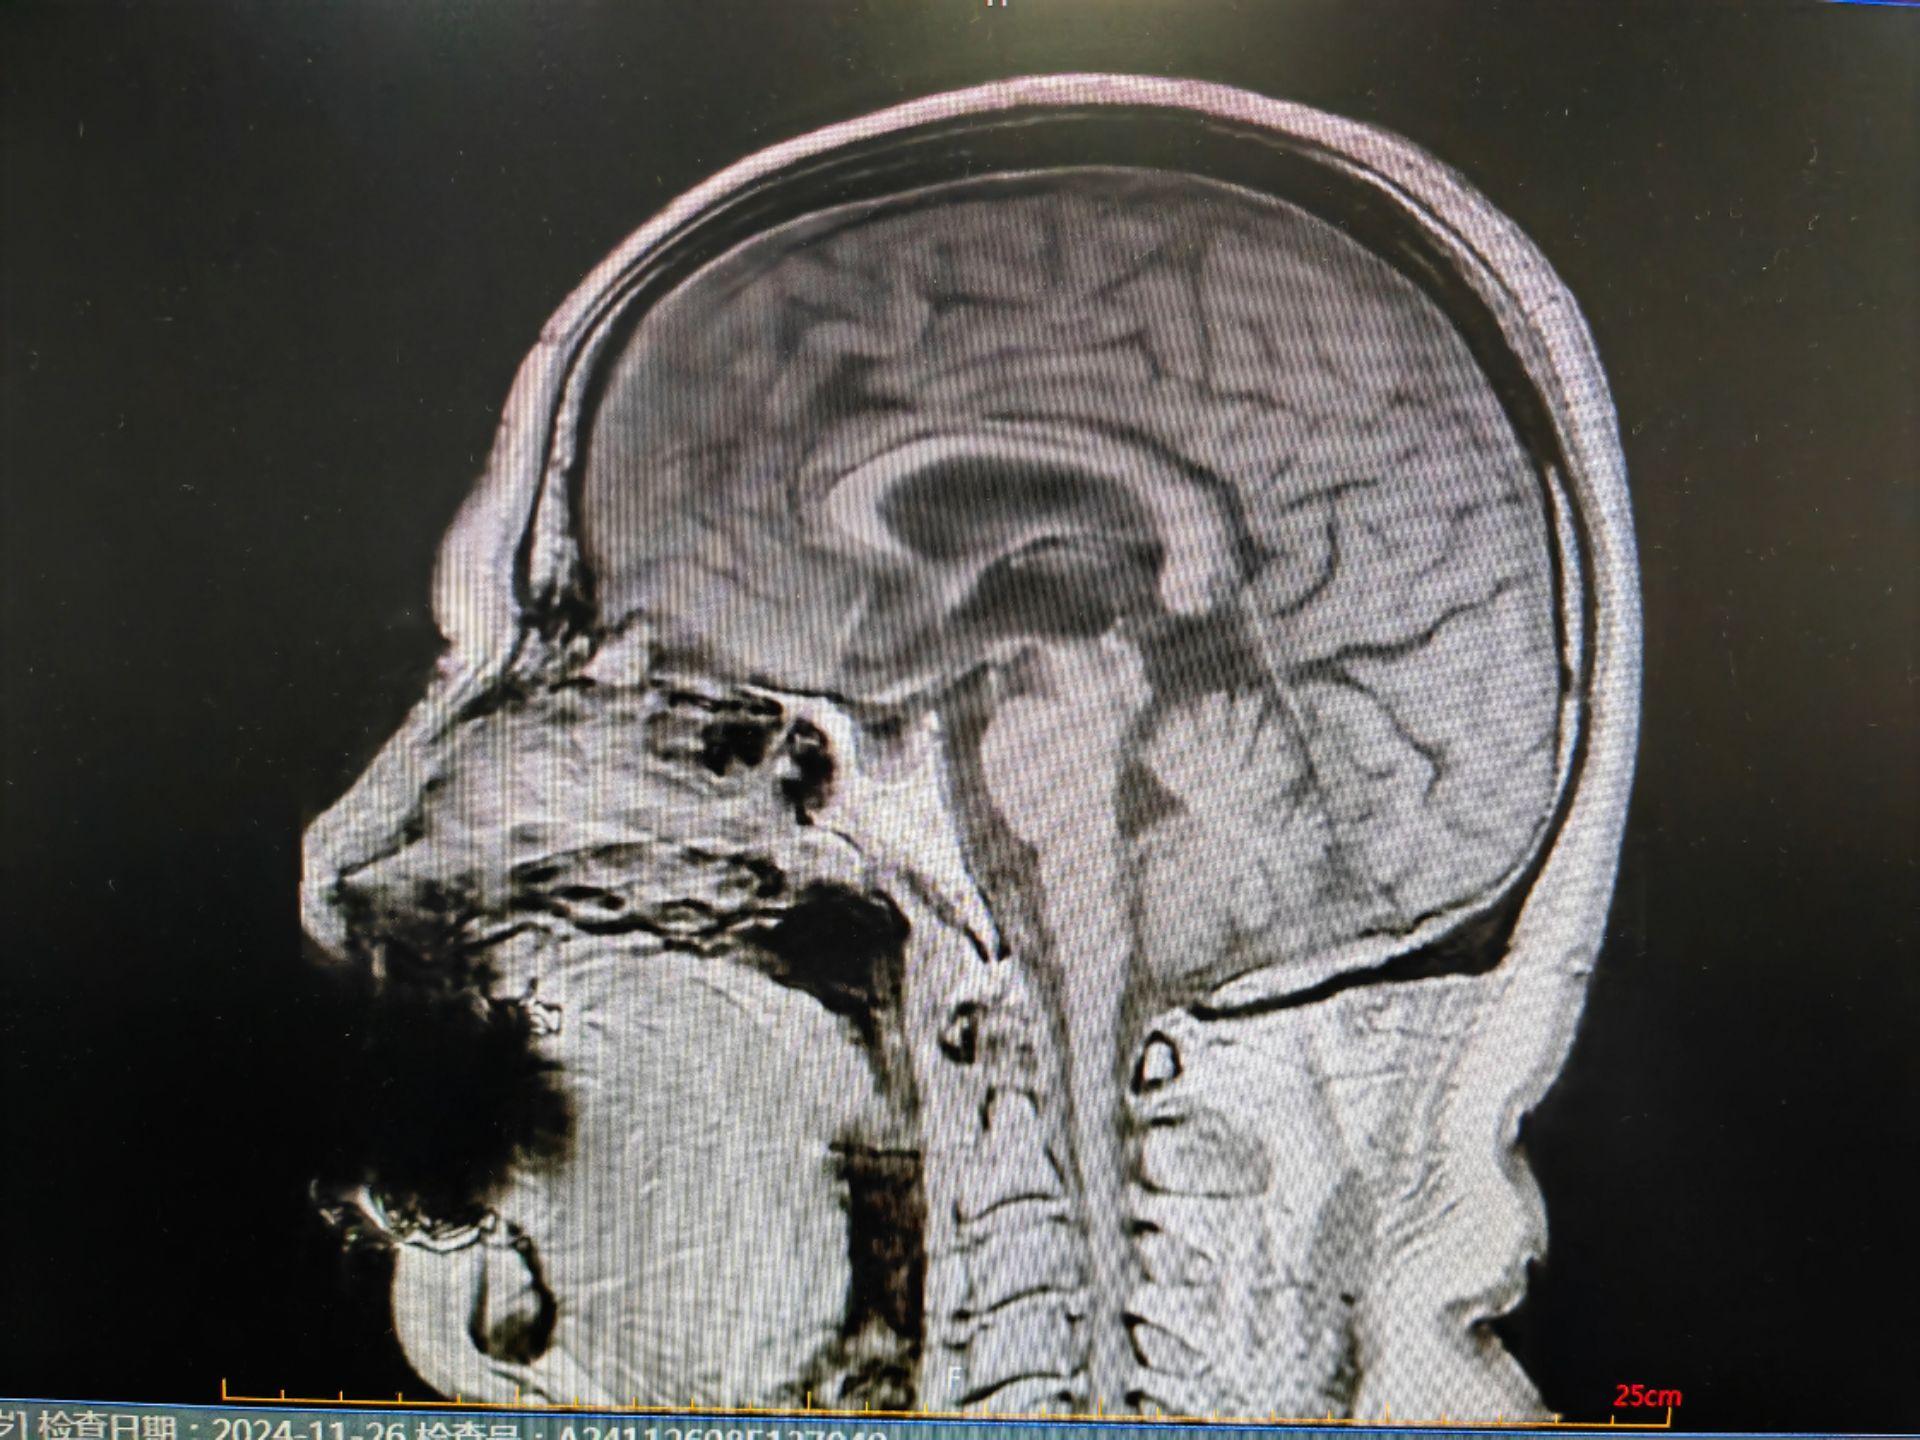

蜂鸟征,米老鼠征,牵牛花征。蜂鸟征 米老鼠征 牵牛花征 进行性核上性麻痹 PSP。PSP 是一种发生于中老年人的中枢神经系统变性疾病,临床表现为轴性强直,垂直性眼球运动障碍, 早期出现反复向后跌倒。但临床诊断为很可能 PSP 患者,经病理诊断证实的阳性预测率约 80%~90%。其临床病理特征为:中脑顶盖和被盖萎缩、黑质色素脱失,第三、四脑室及导水管轻度扩张。